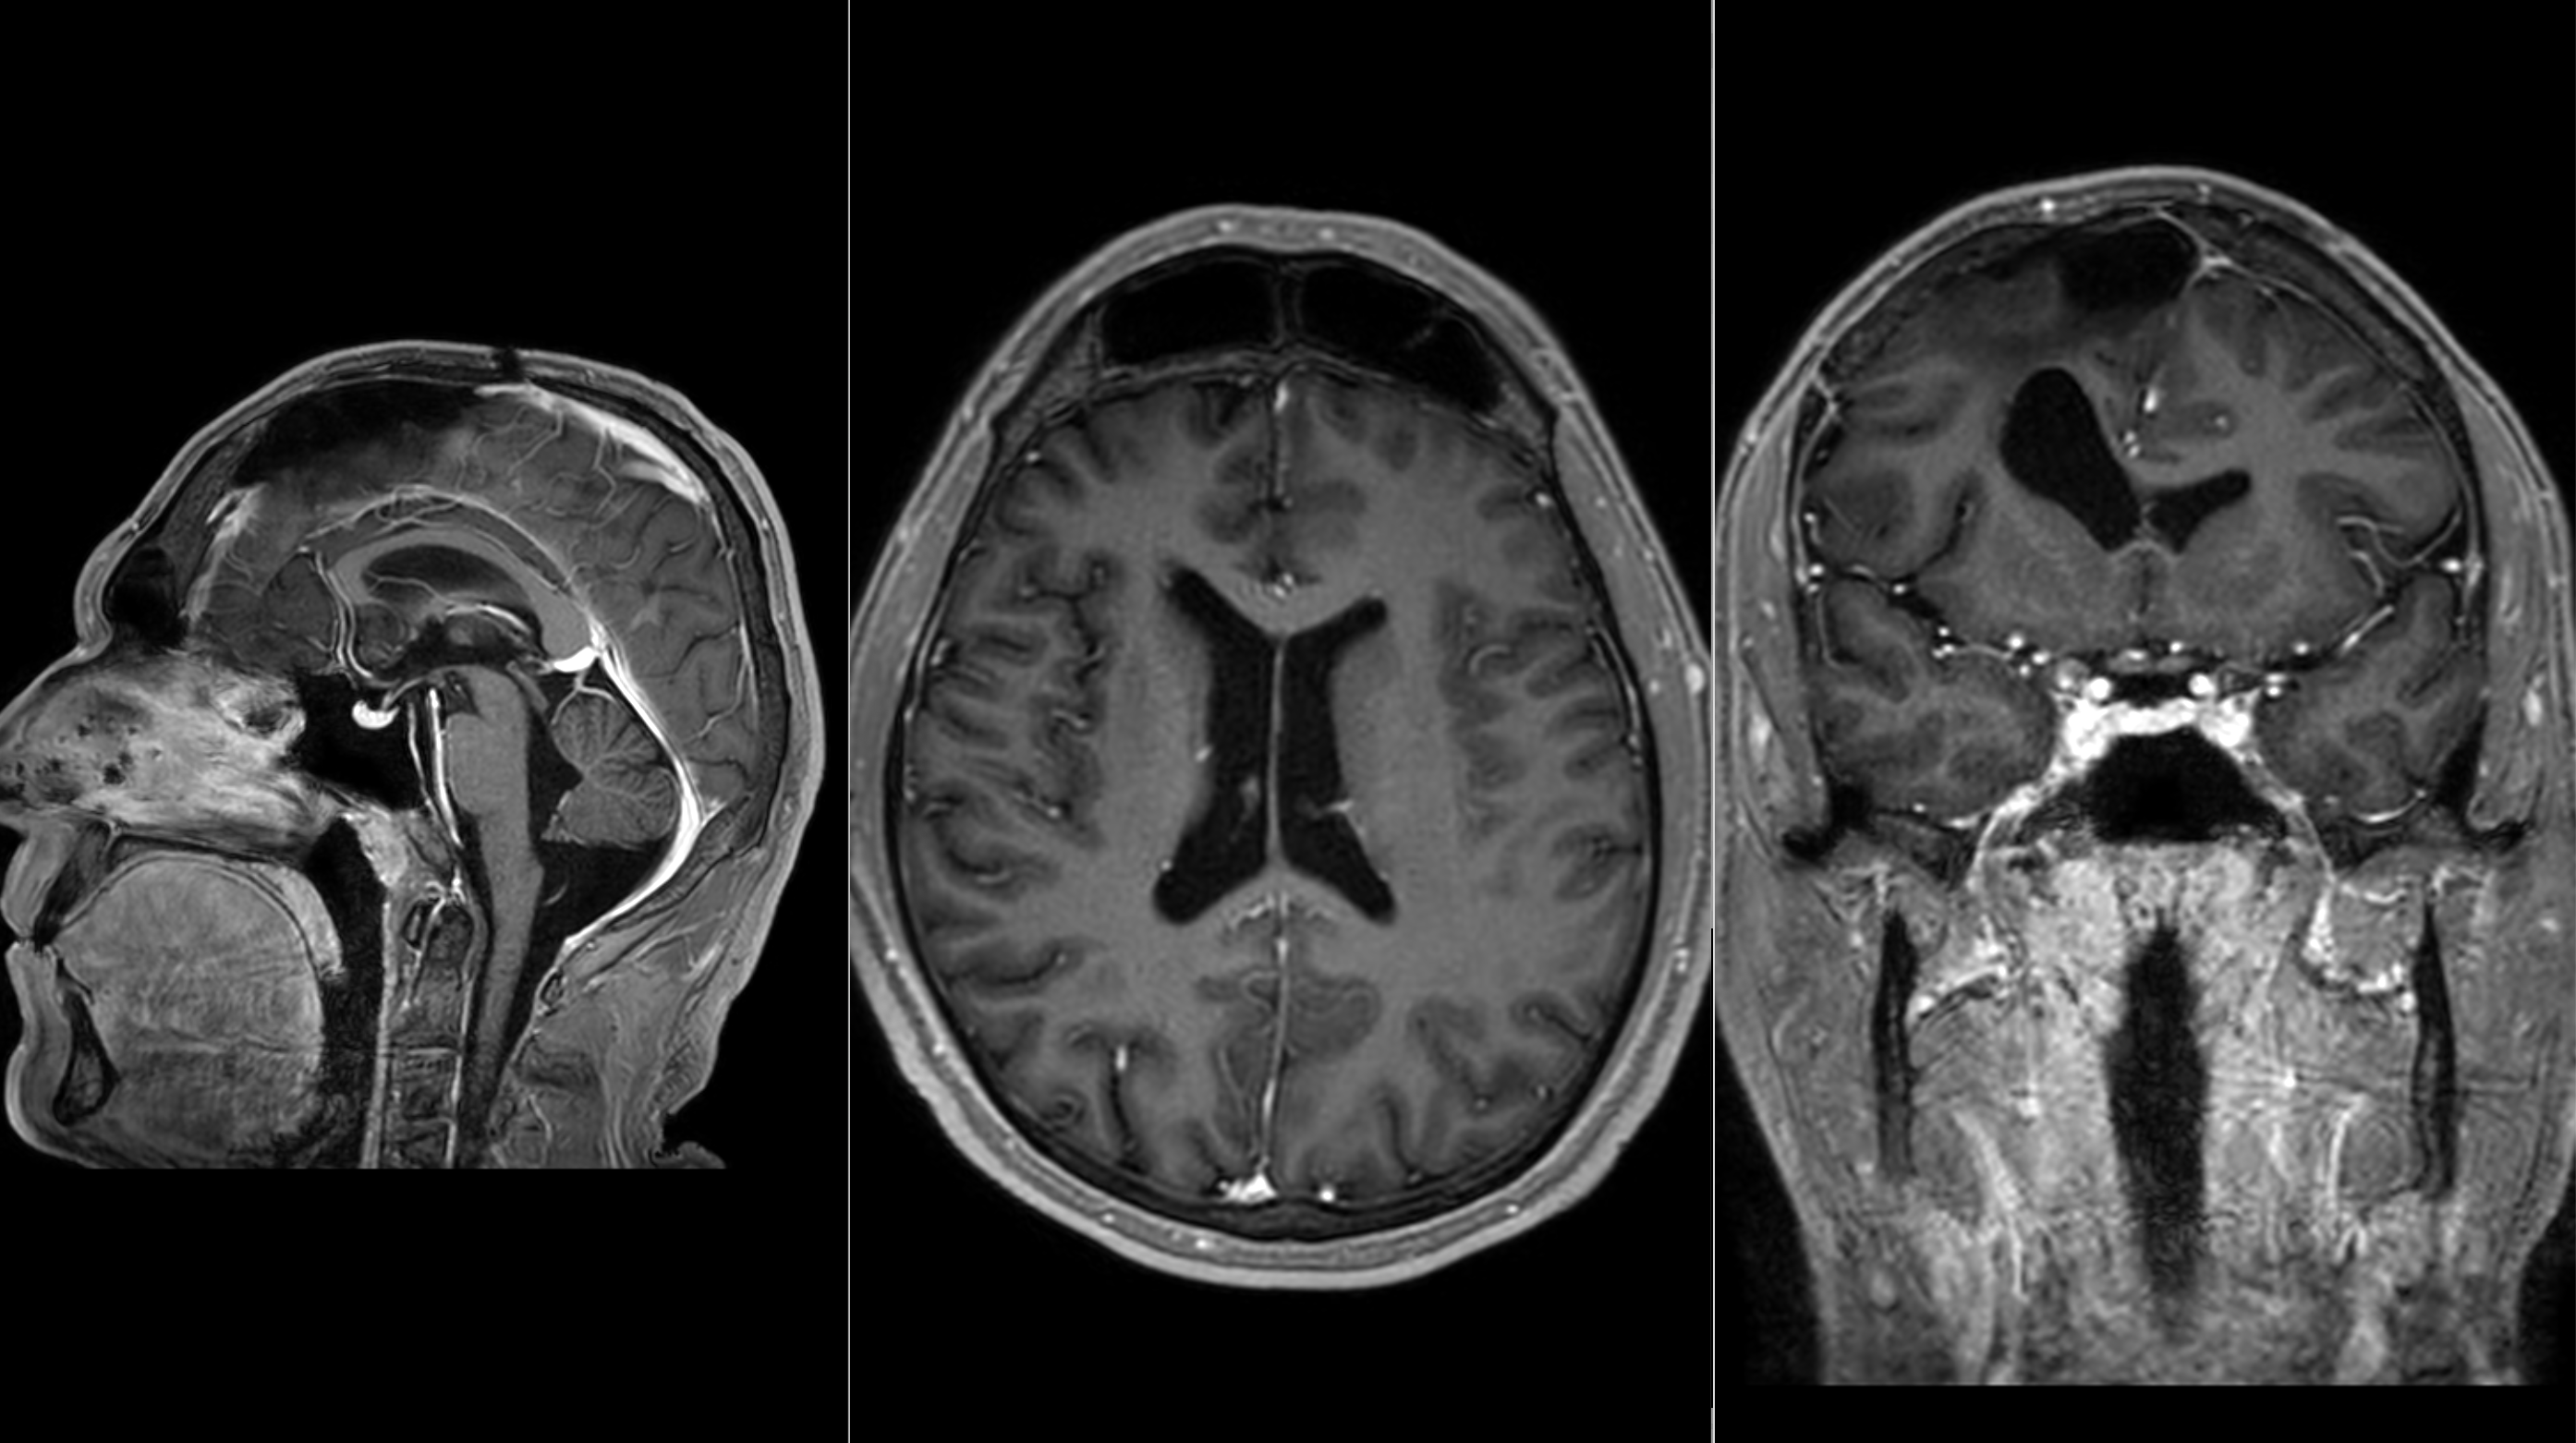

A male patient in his mid-30s presented with nearly a year of progressively debilitating headaches accompanied by profound fatigue and reduced functional stamina. As symptoms escalated and began to affect daily activity, diagnostic imaging revealed a large intracranial mass consistent with a giant meningioma - a benign, dural-based tumor whose size and mass effect can create urgent neurologic risk despite non-malignant pathology.

Given the tumor’s substantial volume and the degree of compression on adjacent brain structures, the patient was referred for urgent neurosurgical evaluation at Adventist Health Glendale, where he was assessed by neurosurgeon Dr. Yaser Badr.